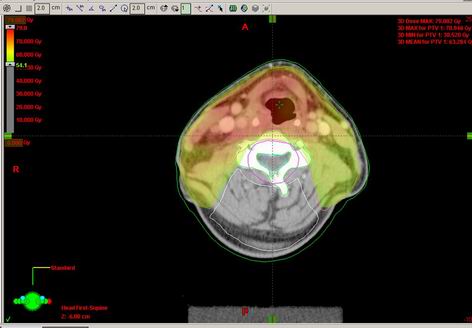

53-letý Z.T.

Karcinom hypofaryngu, recesus piriformis l.dx T2 N2b M0, spinoca

Kurativní RT – konvenční frakcionace

Zakreslení struktur:

DVH:

Dávka > 40Gy:

Dávka > 45 Gy:

Dávka > 54 Gy:

Dávka > 60 Gy:

Dávka > 72 Gy: